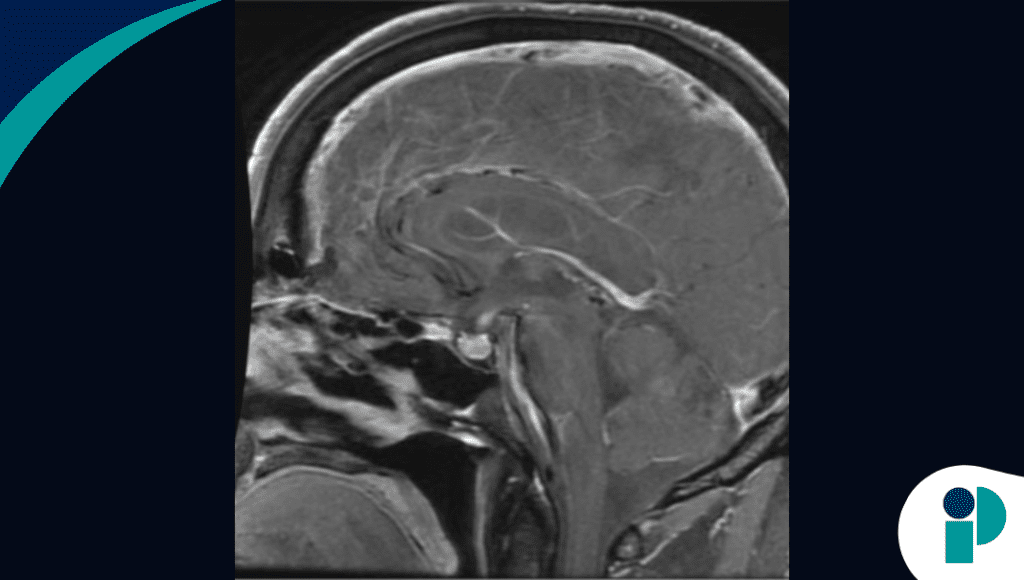

La clave diagnóstica fue un nivel de cortisol sérico marcadamente bajo medido a las 8 de la mañana, compatible con insuficiencia suprarrenal. Estudios posteriores, incluida una resonancia magnética cerebral, evidenciaron hipofisitis, confirmando una insuficiencia suprarrenal central asociada a la inmunoterapia.